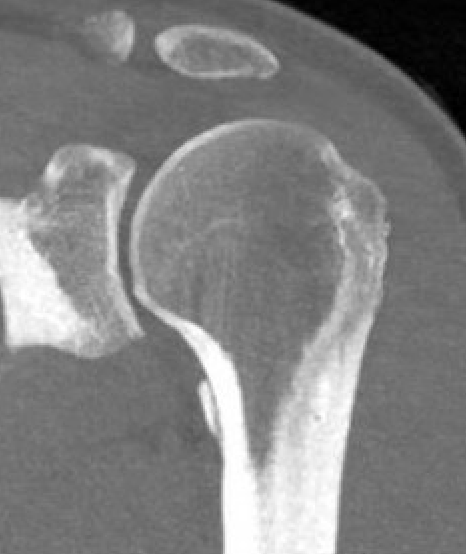

Bony avulsions (BHAGL)

Bony avulsion HAGL